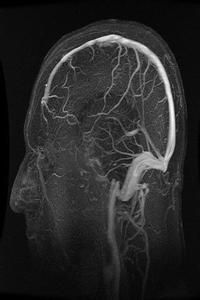

(三)MRI( magnetic resonance imaging )

常規MRI檢查對MS的臨床確診患者MRI陽性率>95%。MRI檢查可見大小不一,類似圓形的T1底信號,T2高信號,常見於側腦室前角與后角周圍,半卵圓中心及胼胝體,或為融合斑,多位於側腦室體部;腦幹、小腦和脊髓可見斑點狀不規則T1底信號及T2高信號斑塊;病程長的多數患者可伴腦室系統擴張,腦溝增寬等白質痿縮徵象。多發性硬化引起的震顫